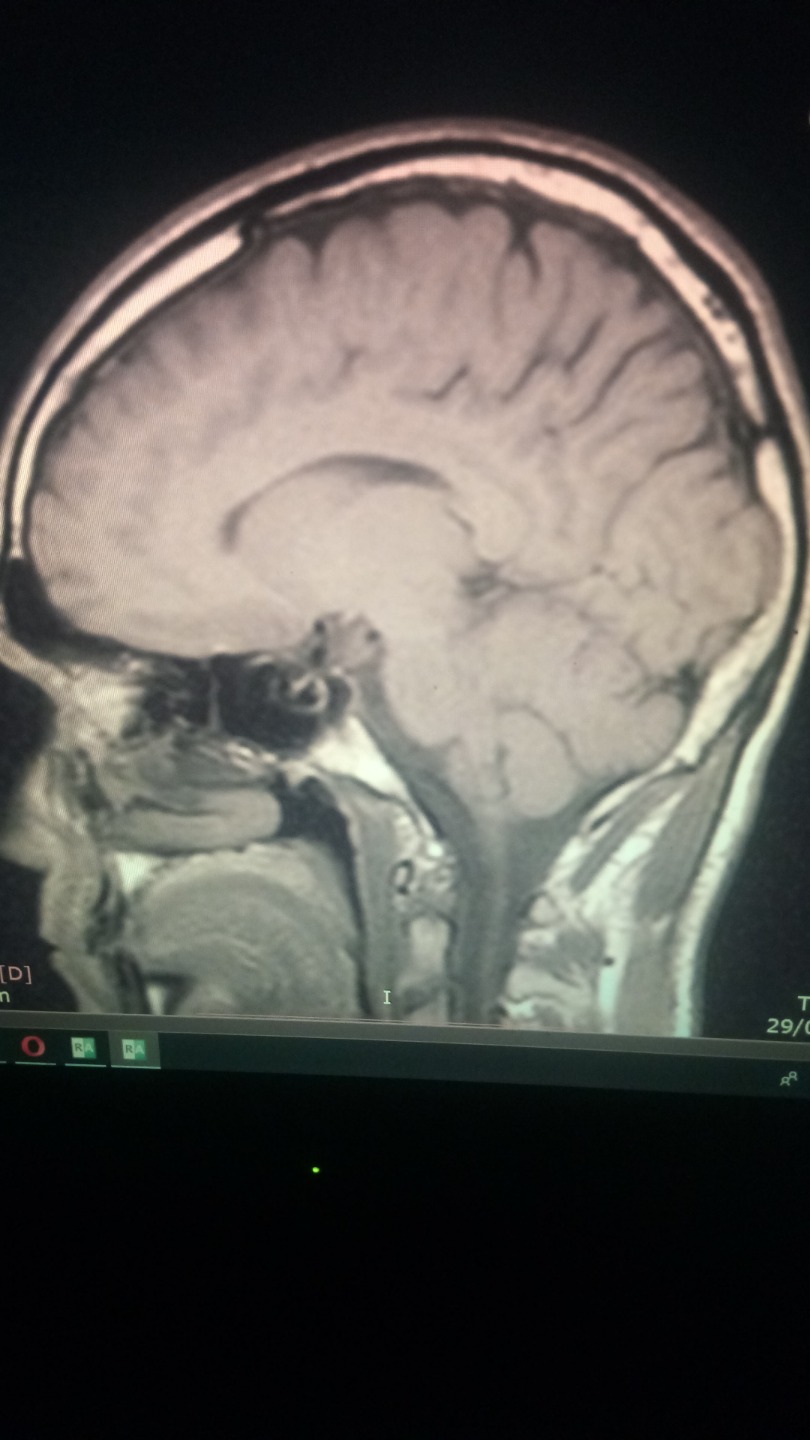

PD : Will atach a photo of my brain, if anyone knows how to read mri scans and know what is going on on my brain is real apreciated. I just think is a infection that somehow is cicatrized thanks to mms.

Neurologist says I have nothin, I dont believe him.

the infection ( look at the pics of my brain mri, i had not headaches, nor nothing, but my brain was having an infections, i noticed something was wrong because i had insomnia for 3 months , like real hardcore insmonia, visual snow, poor memory and concentration, joint paints, dificulti breathing (babesia like simptom) coughfin, and stuff like that. But it wasnt like a normal type of cold. It was weird. I got headeaches when I started to take mms, specially big doses of 15 drops. less than that and standart protocol 1000 was not effective.